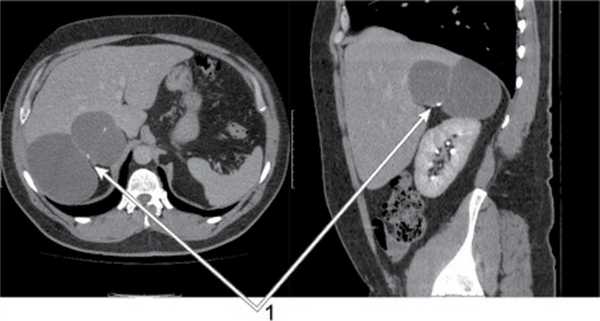

Клинический пример № 1. Пациентка Д., 29 лет. Диагноз: аденома VII сегмента печени (рис. 4). В положении пациентки на левом боку после пересечения правой треугольной связки и диссекции area nuda печени выполнена атипичная резекция VII сегмента с новообразованием. Послеоперационный период без осложнений. Выписана на 6-е сутки после операции.

Рис. 4. Клинический пример № 1: объемное образование в VII сегменте печени (1).